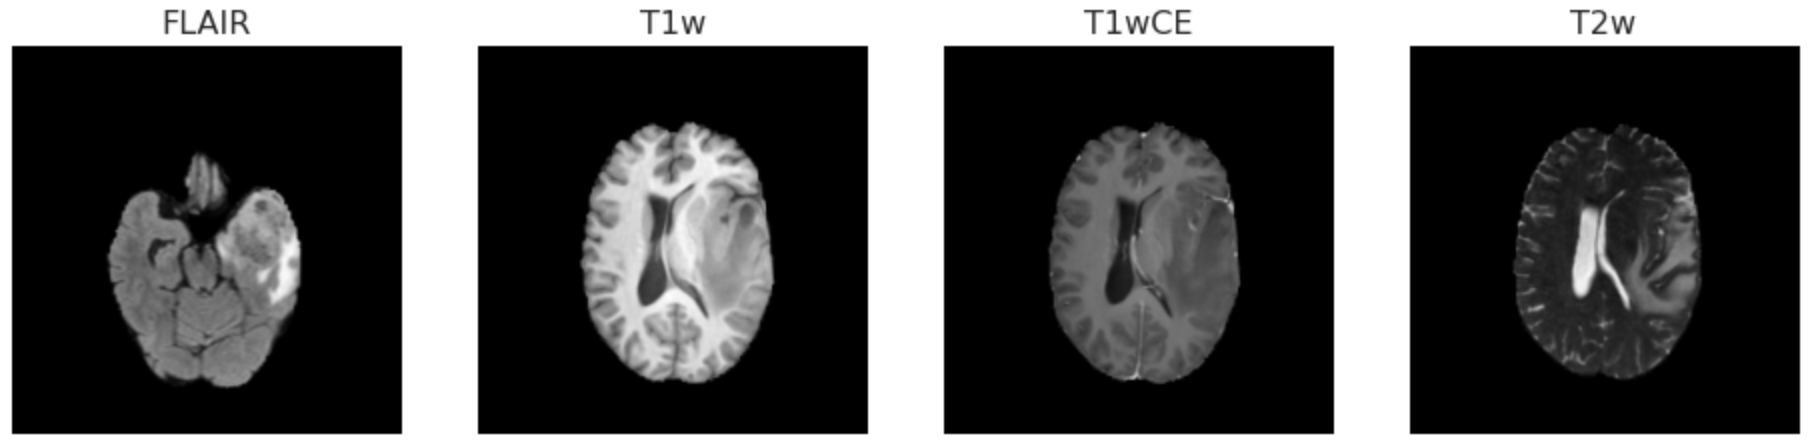

The radiogenomic classification task dataset contains multi-parametric MRI (mpMRI) scans for 585 patients with glioblastoma. Patients fall into two categories based on their MGMT status: methylated MGMT (1) and unmethylated MGMT (0). The dataset is evenly distributed across the two classes, with 307 methylation cases and 278 unmethylated cases, as shown in Figure 1(a). As a result of the balanced nature of the dataset, the learning algorithm is not expected to show skewing behavior. In addition, metadata such as modality, orientation, and MRI machine-specific information are included in the Digital Imaging and Communications in Medicine (DICOM) header of the images. Images have variable slice thicknesses ranging from 0.43 to 6 mm. Four imaging modalities are used to capture each patient’s images: T1-weighted pre-contrast (T1), T1-weighted post-contrast (T1wCE (Gadolinium)), T2-weighted (T2), and T2 Fluid Attenuated Inversion Recovery (T2-FLAIR). Each of these MRI modalities highlights a different aspect of the target area which, when used together, can assist in better localizing the tumor region than can one modality alone. Table 1 depicts the differences between the MRI modalities.

The number of slices for each patient differs across the modalities mentioned above. Patients with the IDs [00109], [00123], and [00709] are excluded from the dataset because the quality of their images is unacceptable and we do not want them to affect our analysis. Furthermore, MRI scans come in three orientation planes, including coronal, axial, and sagittal. Figures 1(b) and 1(c) display the distribution of scans among various MRI modalities and orientations, respectively. The different scan modalities for some patients were saved in the same orientation plane, but not for all patients. Figure 2 shows four random slices for two patients displaying the four modalities and the existence of the same and different orientations for different patients within the dataset.